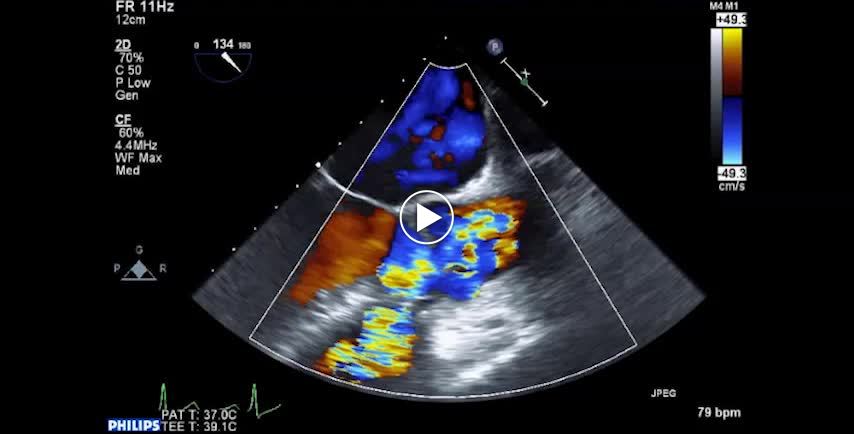

• 図4 Valsalva洞動脈瘤の右室破裂(VSD合併例) b